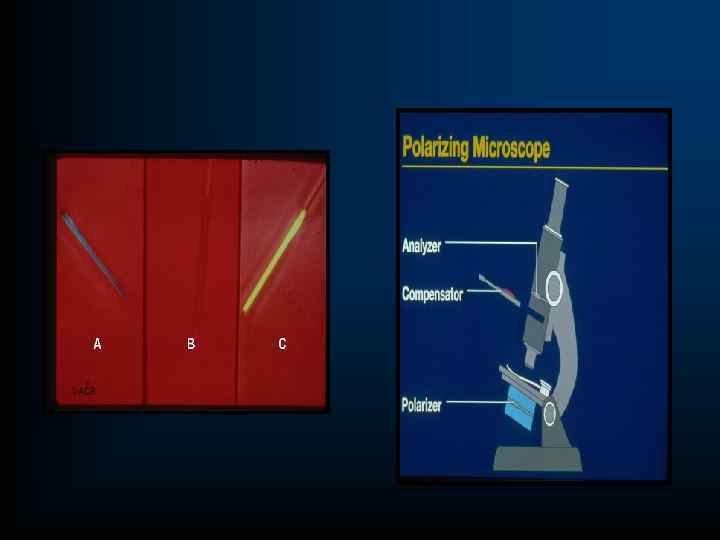

ЛАБОРАТОРНО-ИНСТРУМЕНТАЛЬНЫЕ МЕТОДЫ 1. ОАК, ОАМ 2. Биохимическое исследование крови: уровень мочевой кислоты ( ж-0, 24+0, 06 ммоль/л. , м. – 0, 306+ 0, 06 ммоль/л); глюкозы, липидный спектр 3. Суточная экскреция уратов с мочой (механизм гиперурикемии): -более 800 мг-повышено образование; -менее 800 мг –нарушено выведение. 4. Исследование синовиальной жидкости -цитоз до 10 -20 000 клеток/мм, преимущественно нейтрофилов; -в поляризационном микроскопе – выявление внутриклеточно расположенных кристаллов урата натрия желто-оранжевого цвета. 5. Рентгенологическое исследование –достоверные признаки – не ранее 5 лет: -симптом «пробойника» , -симптом «вздутия костного края» -деструкция не только субхондрального участка кости, но и всего эпифиза

ЛАБОРАТОРНО-ИНСТРУМЕНТАЛЬНЫЕ МЕТОДЫ 1. ОАК, ОАМ 2. Биохимическое исследование крови: уровень мочевой кислоты ( ж-0, 24+0, 06 ммоль/л. , м. – 0, 306+ 0, 06 ммоль/л); глюкозы, липидный спектр 3. Суточная экскреция уратов с мочой (механизм гиперурикемии): -более 800 мг-повышено образование; -менее 800 мг –нарушено выведение. 4. Исследование синовиальной жидкости -цитоз до 10 -20 000 клеток/мм, преимущественно нейтрофилов; -в поляризационном микроскопе – выявление внутриклеточно расположенных кристаллов урата натрия желто-оранжевого цвета. 5. Рентгенологическое исследование –достоверные признаки – не ранее 5 лет: -симптом «пробойника» , -симптом «вздутия костного края» -деструкция не только субхондрального участка кости, но и всего эпифиза